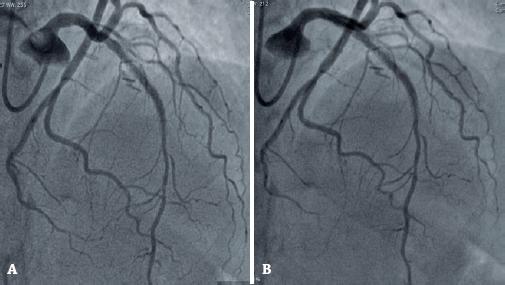

Figura 3

Estudo hemodinâmico (2020). (A) Evidência de stent pérvio em descendente anterior. (B) Evidência de stent pérvio em descendente anterior.